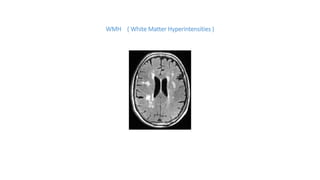

WMH ( White Matter Hyperintensities )

WMH ( WhiteMatter Hyperintensities )